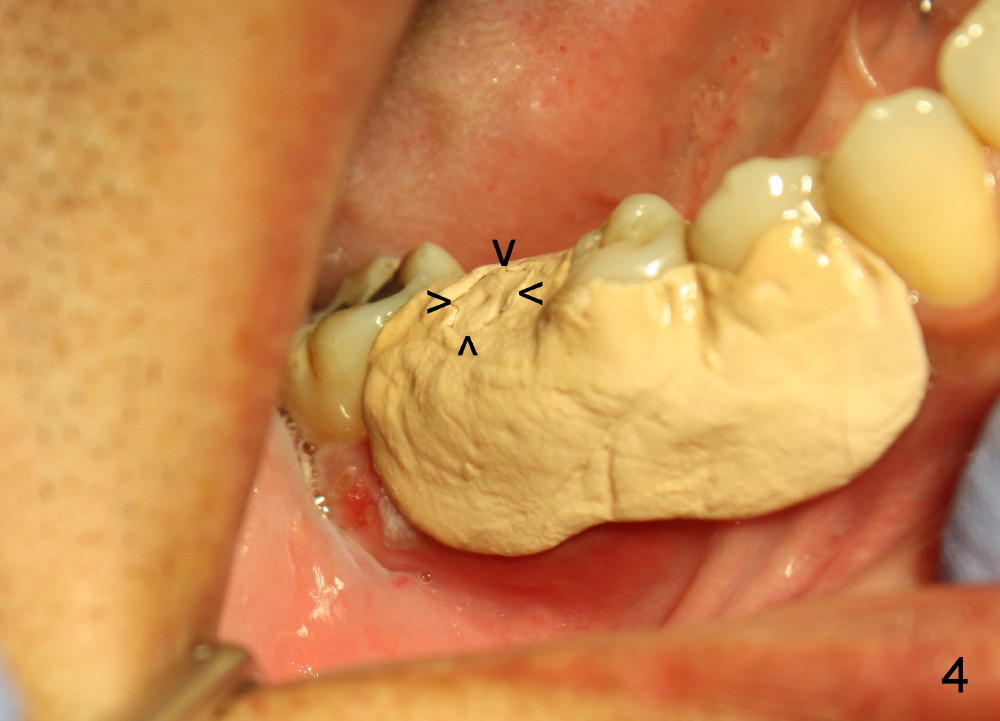

The patient returns for extraction and immediate implant after 7 days of oral Amoxicillin. There is a deep pocket mesiolingually in addition to the mesiobuccal fistula (Fig.1 <). The metal crown and then the tooth are sectioned. The crack of the mesial root is confirmed during extraction. The coronal portion of the mesiobuccal plate is defective, corresponding to the fistula. Both the mesial and distal sockets are large with a thin septum in between. Osteotomy is established at the base of the septum, slightly toward the mesial socket, as evidenced by a 5x20 mm tap in place (Fig.2). Finally, a 7x17 mm implant is placed (Fig.3 I; A: abutment; G: bone graft). The insertion torque is more than 60 Ncm.

Due to the presence of the abutment (Fig.4 arrowheads), the perio dressing remains in place 7 days postop.